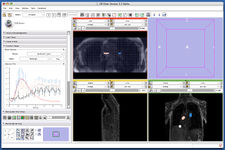

4D Image Viewer (Junichi Tokuda)

The FourD Analysis module was designed for time series analysis (Junichi Takuda)